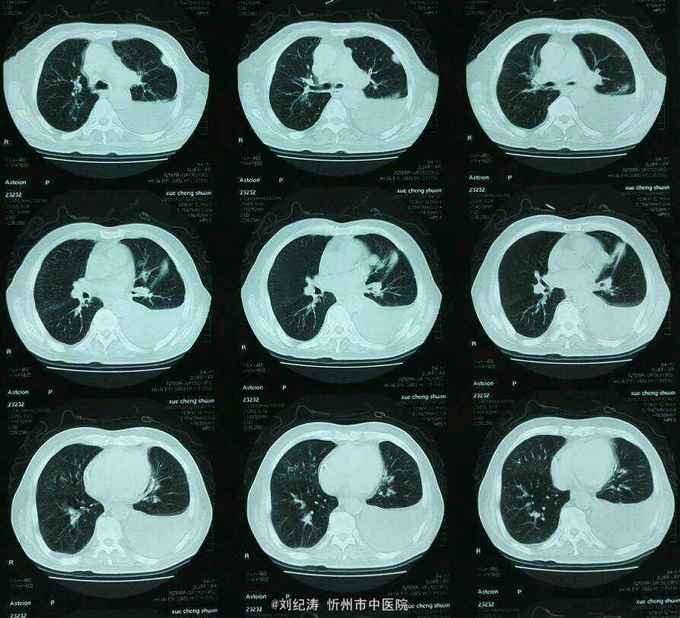

查体:ECOG评分:3分,生命指征平稳,浅表淋巴结未触及明显肿大,双眼睑无水肿,唇无发绀,颈软,双侧胸廓对称,左肺语颤增强,左肺呼吸音消失,右肺呼吸音粗,可闻及哮鸣音,心律齐,腹平软,肝脾肋下未触及,移动性浊音阴性,肠鸣音3次/分,双下肢无水肿。 辅助检查:血常规(2016.1.1):WBC:10.6*109/L,RBC:4.69*1012/L, PLT:165*109/L ,HGB:167g/L.生化(2016.1.1):谷丙转氨酶11U/L,谷草转氨酶11U/L,总蛋白60g/L,白蛋白33g/L,尿素:9.8mmol/L,肌酐:123umol/L,尿酸:251 umol/L,血糖:7.37 mmol/L;电解质:钾:4.79mmol/L,钠:123.5 mmol/L,氯:85.7 mmol/L,钙:2.03 mmol/L。肺部CT(2016.1.1):左肺完全萎缩,左侧胸腔大量积液,右肺未见异常,纵膈轻度右移,未见明显肿大淋巴结。